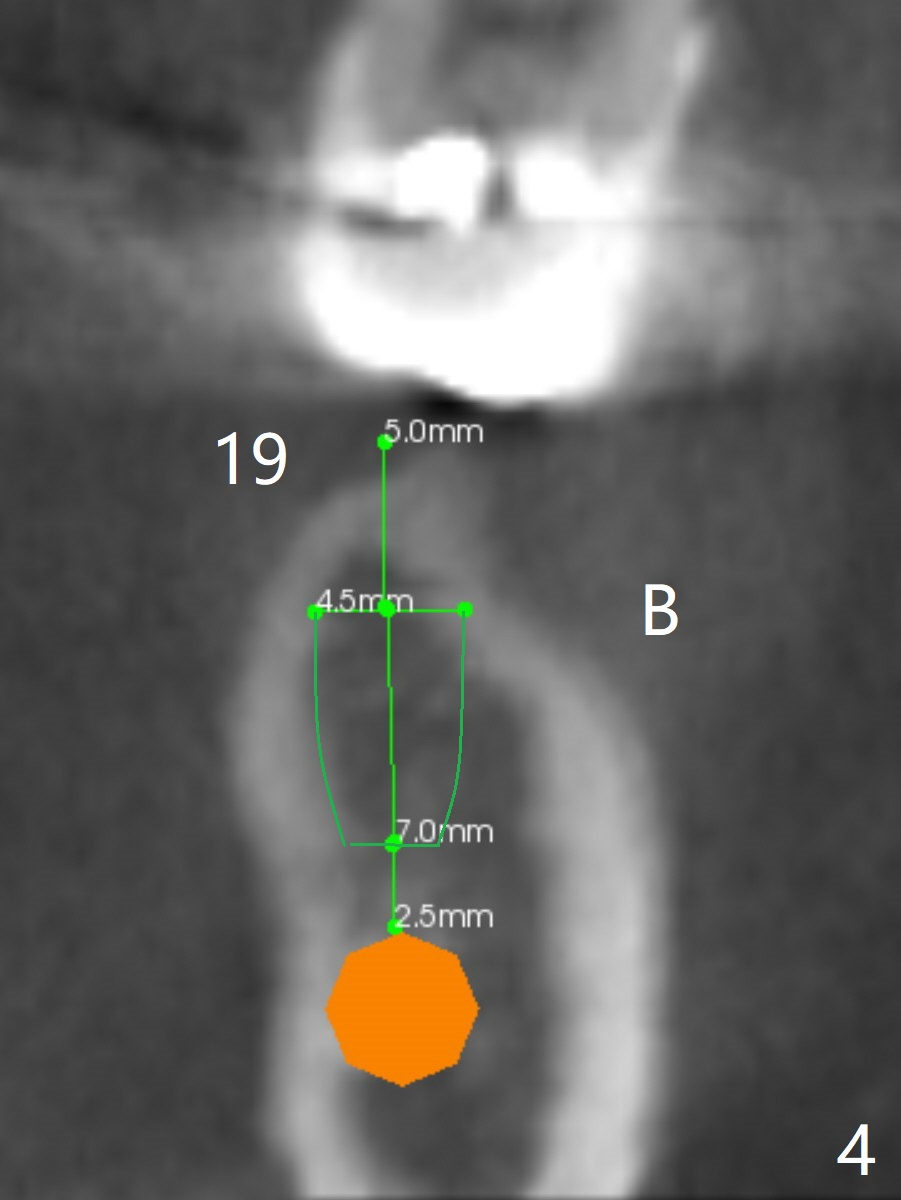

A 45-year-old woman returns to seek treatment for the recemented lower left FPD with open margin at #18 (Fig.1 *). It appears that two implants will be placed (Fig.2,3). Because of the narrow crest at #19, the ridge will be reduced before placement of a 4.5x7(4) mm Magicore (Fig.4). A 5x9(2 or 3) mm one will be placed in the mesial slope of the extraction socket (Fig.2,3,5). Alginate impression will be taken for wax up and surgical stent.